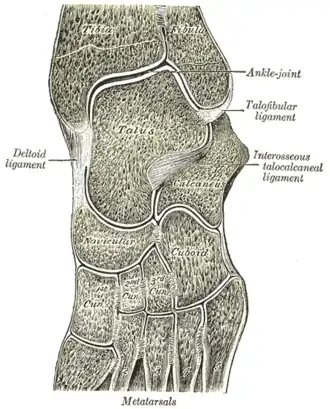

Oblique section of left intertarsal and tarsometatarsal articulations, showing the synovial cavities.

Oblique section of left intertarsal and tarsometatarsal articulations, showing the synovial cavities. -